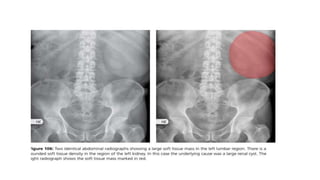

Either by increase in the overall size of one of the solid organs or by a large

tumor in the abdomen.

Incidental finding as first IOC – ultrasound.

•Renal masses

•Pelvic masses

RADIOLOGICAL SIGNS :

•Large soft tissue density (light grey)mass

•Loops of bowel often displaced by the mass

•Location gives a clue

RUQ – liver , right kidney

LUQ – spleen ,left kidney , fluid filled stomach

Lower abdomen – ovaries,uterus , distended urinary bladder.